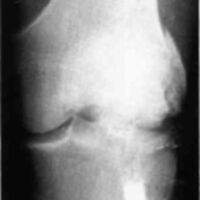

A twenty-nine year old male sustained a high caliber gunshot wound to the left knee (Fig. 4), traversing the lateral femoral condyle through the joint space and through the lateral tibial plateau. Open reduction internal fixation (ORIF) and ligamentous repairs were made. Postoperatively, the patient was placed in a standard cast brace due to the inability to provide adequate medial-lateral stability of the knee surgically (Fig. 5). The cast brace was attached to a continuous passive motion dynamic suspension system to restore and maintain motion (Fig. 6). At the time of the initial cast bracing, the patient had considerable soft tissue edema about the knee. The use of passive motion quickly reduced that swelling to the point where the cast brace provided little support. After one week, the cast brace was reapplied with the addition of a varus producing strap (Fig. 7) and the patient began ambulation training and was discharged. (If atrophy or swelling should continue, the varus producing strap can be easily adjusted to maintain force on the knee and another cast change would not be required).

Figure 1:

Figure 4:

Figure 5: